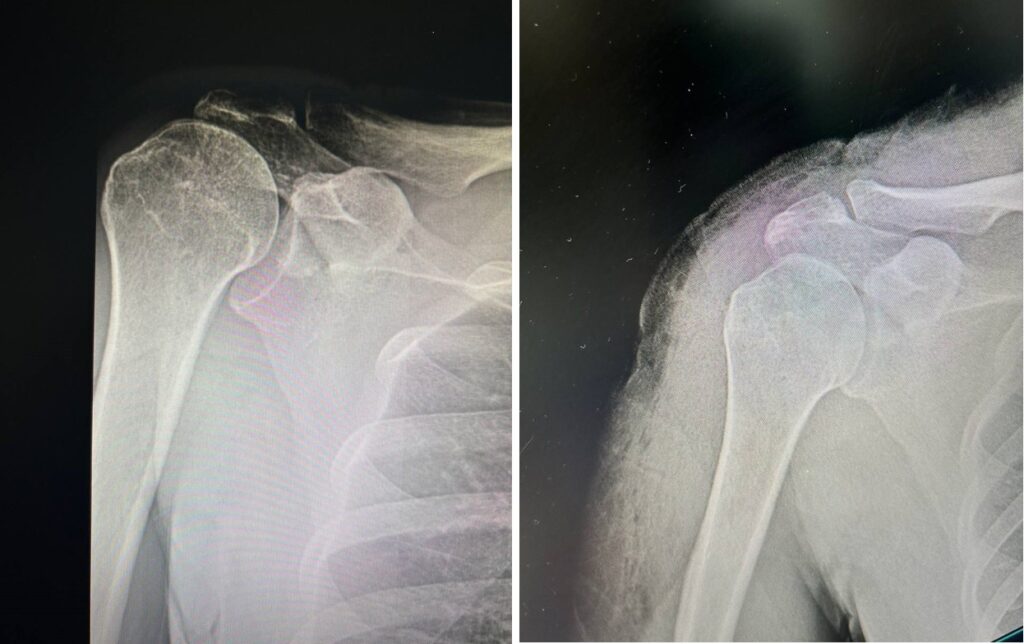

Гэмтэл согог судлалын үндэсний төвийн салбар эмнэлгийн Спортын гэмтлийн тасгийн эмч, мэргэжилтнүүд Монголд анх удаа мөр эргүүлэгч шөрмөсний сэргээх боломжгүй урагдалд үений дурангийн мэс заслын аргаар гуяны шөрмөс шилжүүлэн нөхөн сэргээх эмчилгээг амжилттай хийлээ.